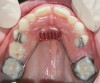

Fig 6. Patient with cleft palate treatment history and underdeveloped craniofacial growth, facial view (Fig 6) and occlusal view (Fig 7).

Figure 6

Fig 7. Patient with cleft palate treatment history and underdeveloped craniofacial growth, facial view (Fig 6) and occlusal view (Fig 7).

Figure 7

Although the face is a 3-dimensional structure, craniofacial growth modification is a topic that may be stratified by reviewing the transverse, vertical, and anterior-posterior dimensions. A transverse growth inadequacy is often illustrated in the form of a posterior (and often anterior) crossbite.21 The most common cause of this inadequacy is an underdeveloped maxilla, or, alternatively, an overdeveloped mandible; oftentimes a combination of these characteristics is the source of the problem. One example is a patient who has had cleft lip/palate repair, which may lead to craniofacial growth restriction in all dimensions (Figure 6 and Figure 7). When considering the transverse dimension, the most common treatment for a posterior crossbite is RPE therapy.21 In mild cases, archwire or dental expansion may suffice.